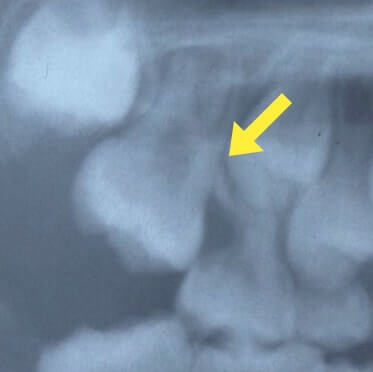

齲蝕(虫歯)